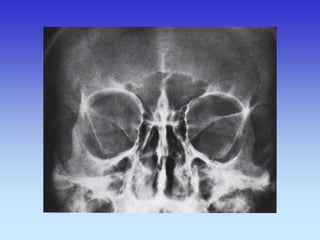

SINUSI PA snimka

1.Nosna pregrada

2.Frontalni sinus

3.Maksilarni sinus

4.Etmoidni sinus